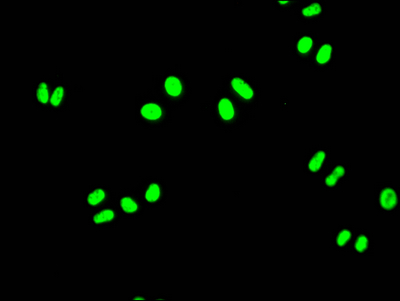

Immunofluorescence staining of Hela Cells with CSB-RA157765A0HU at 1:50, counter-stained with DAPI. The cells were fixed in 4% formaldehyde, permeated by 0.2% TritonX-100, and blocked in 10% normal Goat Serum. The cells were then incubated with the antibody overnight at 4℃. Nuclear DNA was labeled in blue with DAPI. The secondary antibody was FITC-conjugated AffiniPure Goat Anti-Rabbit IgG (H+L).